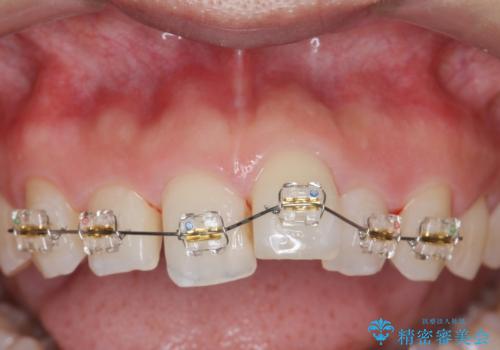

出っ歯に見える前歯の改善 部分ワイヤーとマウスピース矯正

- インビザライン +部分ワイヤー矯正

- 出っ歯に見える前歯の改善を希望され、来院されました。

マウスピースでは改善の難しい歯の動きを部分ワイヤー矯正で整えたのち、奥歯の噛み合わせや細かい歯の並びをマウスピース矯正インビザラインで整えていきます。